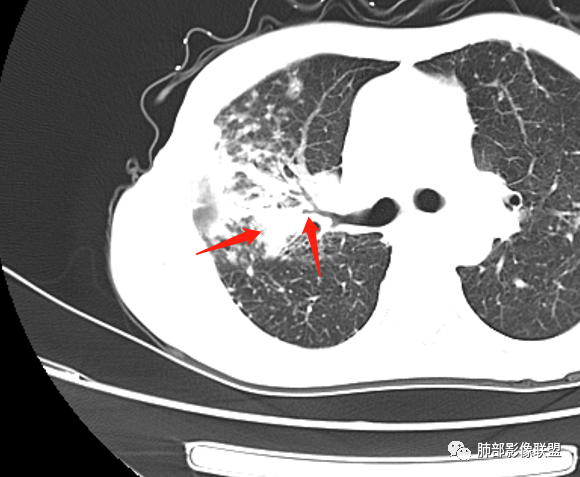

就这里不让人放心,是占位吗?支气管是截断的,没有凹陷或者突出阻断,阻断前稍扩张 医学百科网 | YxBaike.Com

患者老年女性,亚急性起病,主要症状表现为咳嗽、咳痰半月余,查体:双现呼吸音粗,双肺可闻及痰鸣音。胸部CT:双上肺胸膜下可见多发小叶实变影,双上肺可见多发小叶中心性结节及小叶间隔增厚,右上肺后段可见亚段性实变影,内见多发空洞,前段可见GGO及树芽征,后段局部支气管闭塞,肺门淋巴结肿大并钙化。病灶整体:有气道、间质播散,一元论考虑肺结核合并支气管结核可能性大,建议好好查痰;这样病灶:明显实变 空洞 气道播散,若是结核,痰涂片找到抗酸杆菌应该没问题。建议支气管镜检查助诊,了解有无支气管结核及合并腺癌的可能。 医学百科网 | YxBaike.Com

本例肺结核的影像征象:

1、树芽征

2、多发结节,卫星灶

3、小叶间质增厚,有索条影

4、反晕征 医学百科网 | YxBaike.Com